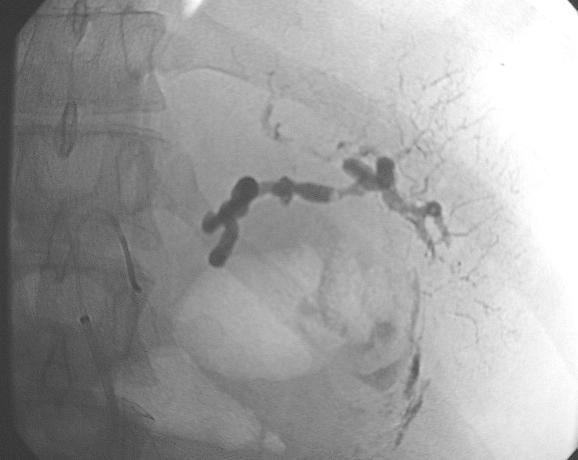

脾动脉瘤